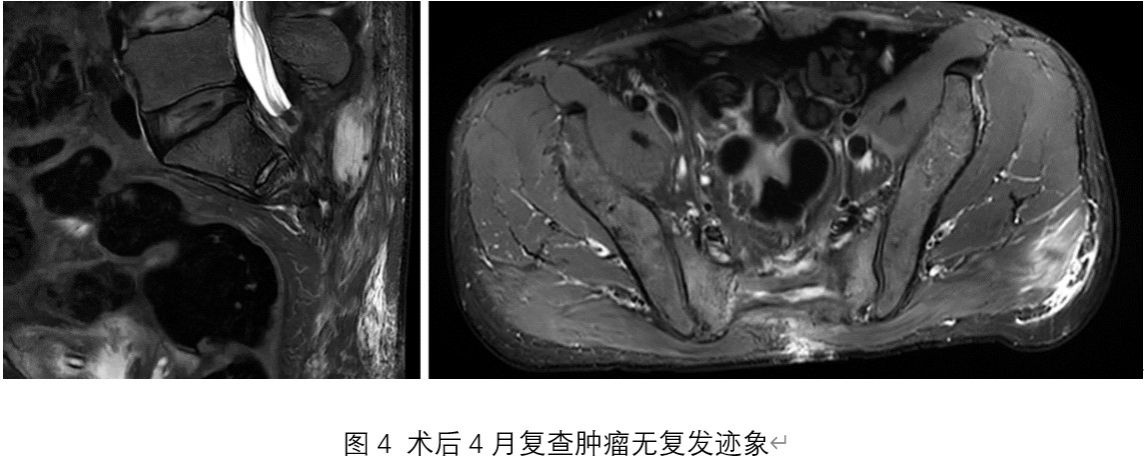

杨先生的故事还在继续。出院后杨先生已回归正常生活节奏,定期接受随访与康复指导,本次术后4月复查肿瘤无复发,膀胱造瘘已完成,相关护理及肠造口也在规范进行中,生活质量逐步提升。